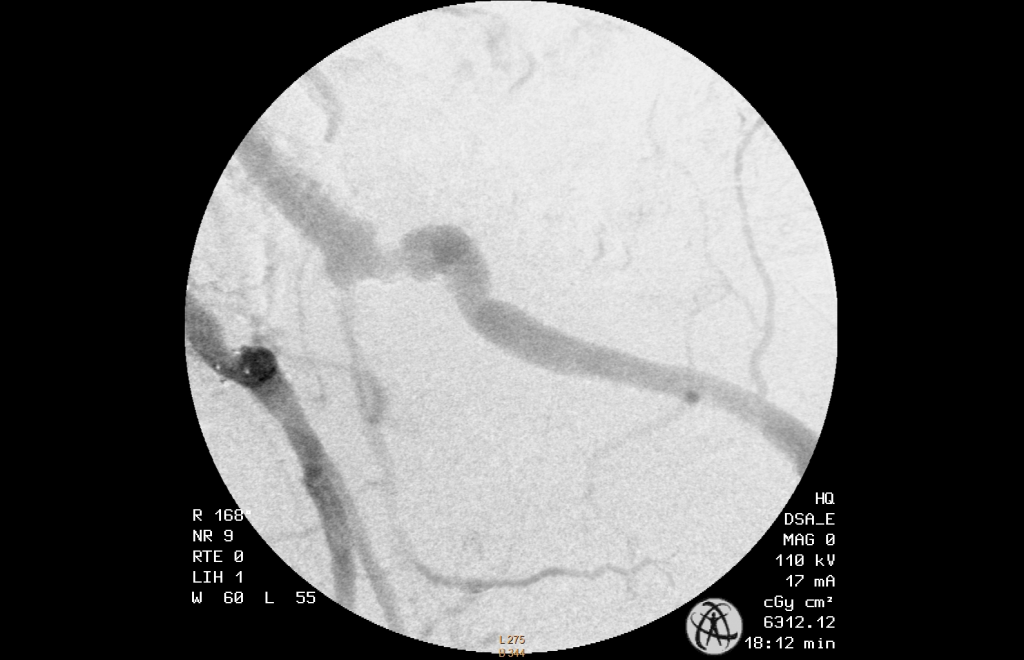

A left brachial access was established and a long sheath placed at the entry of the hypogastric artery. Afterwards it was easy to anchor the guidewire in the small deepening, enter and cross the leasion with the help of a support catheter. The correct intraluminal position past the leasion was confirmed. After pre-dilatation the leasion was stented with a 5mm BMS .

The patient described a pain relief and the 6 month follow-up showed a patend hypogatsric artery.